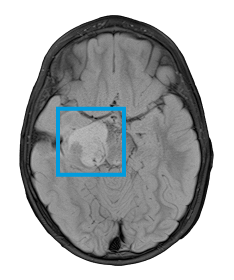

The first and only type II RAF inhibitor for BRAF alterations in relapsed or refractory pediatric low-grade glioma (R/R pLGG)1

OJEMDATM (tovorafenib) is indicated for the treatment of patients 6 months of age and older with relapsed or refractory pediatric low-grade glioma (LGG) harboring a BRAF fusion or rearrangement, or BRAF V600 mutation.